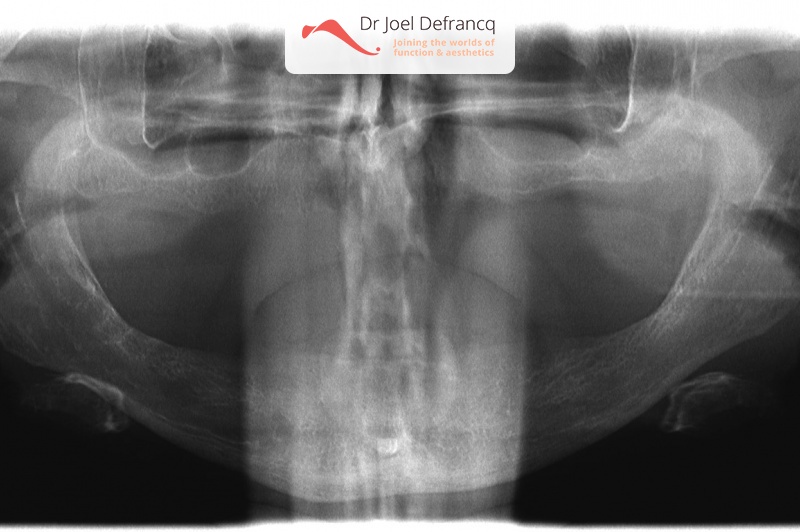

Dentale diagnose

- Klasse I

- Tandeloos